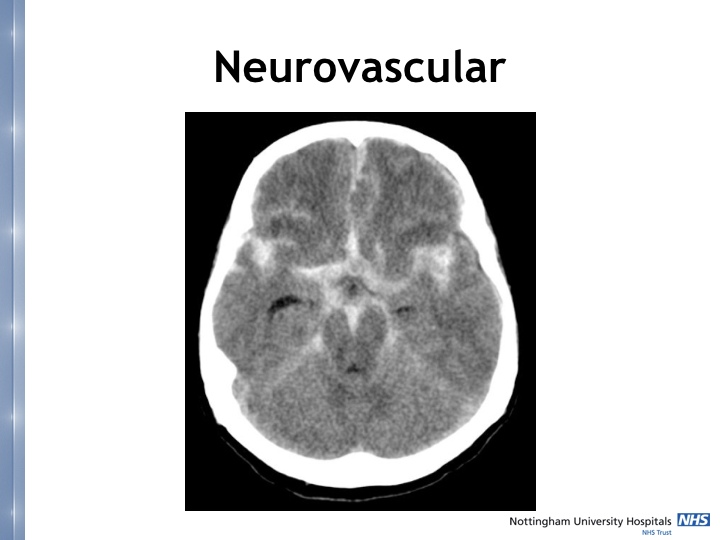

• He discussed neurovascular conditions including the WFNS Grade of Subarachnoid Haemorrhage and the Glasgow Outcome Score